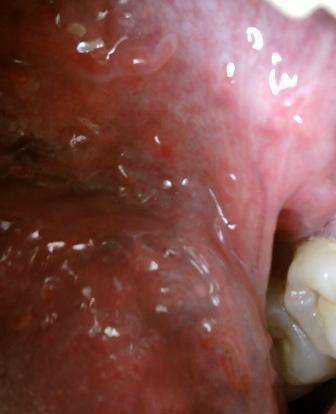

石家庄九州皮肤病医院 > 尖锐湿疣 > > > 高危型尖锐湿疣是怎么一回事尖锐湿疣是一种hpv病毒,并且临床上这种病毒具有好多类型。有低危型和高危型。尖锐湿疣性病具有比较强的传染性,很多人闻之色变。患病之后大家,大家不要沮丧不要灰心,及时去正规的医院进行治疗,坚持治疗,疾病是可以早日康复的。

高危型尖锐湿疣是怎么一回事Hpv病毒在临床上有一百多种,但是大多数是没有任何危害的,感染上病毒之后是不会引起任何饿危害的,尖锐湿疣病毒主要是通过不洁净的性接触来进行传播的,但是除此之外,还会通过间接接触传染和母婴传染而发病。尖锐湿疣病毒是比较顽固的,因此在治疗上有一定的难度,但是并不是不治之症,只要广大患者朋友们可以选择专业的医院,进行规范的治疗,疾病是可以治愈的。